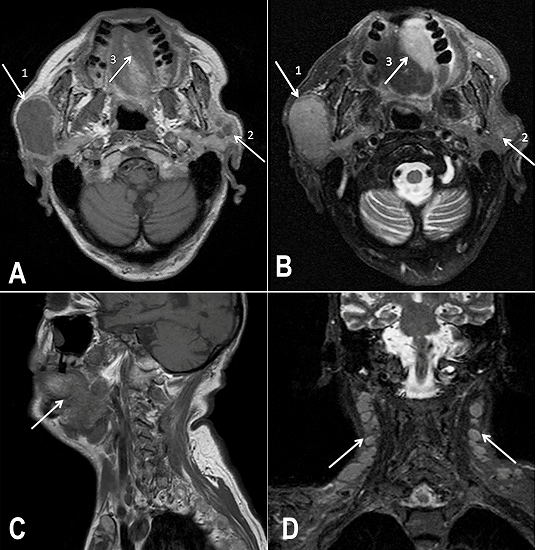

Examination of the right parotid gland by MRI revealed a solid and expansive mass in the superficial lobe, which was characterized by a hyposignal and a hypersignal on a T1-weighted image (T1W) and a T2-weighted image (T2W), respectively. Another two nodular masses were observed in the inferior pole of the parotid gland. MRI also examined the contralateral parotid gland, and three small nodular masses were observed in the superficial lobe, which presented signal features similar to those on the right side. Moreover, a mass involving the left side of the palate showed continuity, with an ipsilateral narrowing of the pharyngeal airspace (Figure 2A and 2B). The posterior two-thirds of the tongue (left side) and both lingual tonsils showed expansive lesions. The epiglottis was posteriorly displaced and the vallecula was obliterated, leading to narrowing of the pharyngeal airspace (Figure 2C). Evidence of expansive masses was also noted on the floor of the mouth and in both sublingual and submandibular areas, without affecting the salivary glands. Bilateral lymphadenopathy was also observed, in contrast with the clinical examination findings (Figure 2D). Considering the clinical and imaging findings, the working diagnosis pointed to a malignant disease.

Of all the available imaging methods, MRI offers the best soft tissue contrast and spatial resolution, with the advantage of not using ionizing radiation.11 For patients with palpable masses in the parotid gland area, MRI is the gold standard method, due to its precision in assessing the exact extension of the mass, the possible invasion of adjacent structures, the perineural spread, and the lymph node staging.7,11,12 Lymphomas exhibit homogenous signal patterns, with hyposignal and hypersignal intensities in T1W and T2W images, respectively.7,12 The clinical features and MRI findings of the current case study highlight the potential of MCL to disseminate—of which physicians should be aware—based on the suggestive multifocal manifestation of the disease.